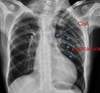

12

A

Consolidación alveolar

How well did you know this?